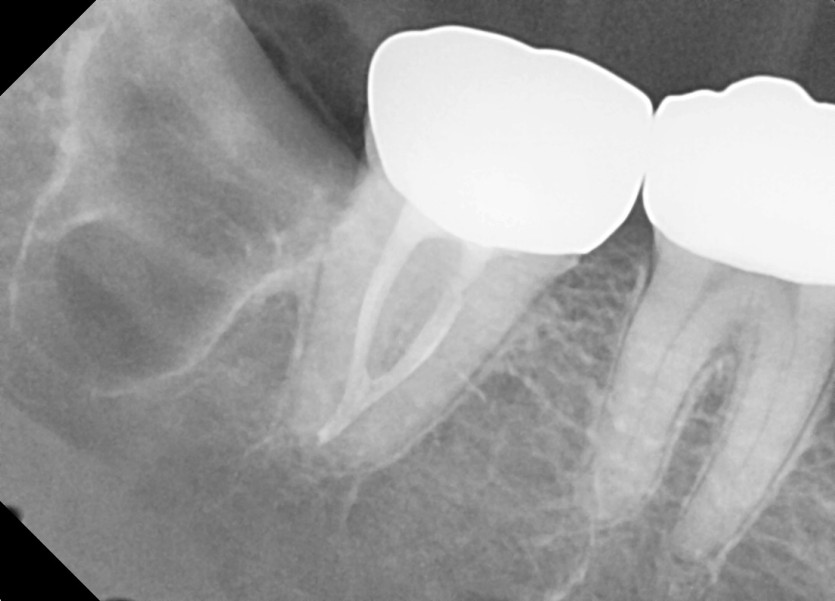

#48 사랑니 발치

구강 외과 전문의가 당일 발치했습니다.